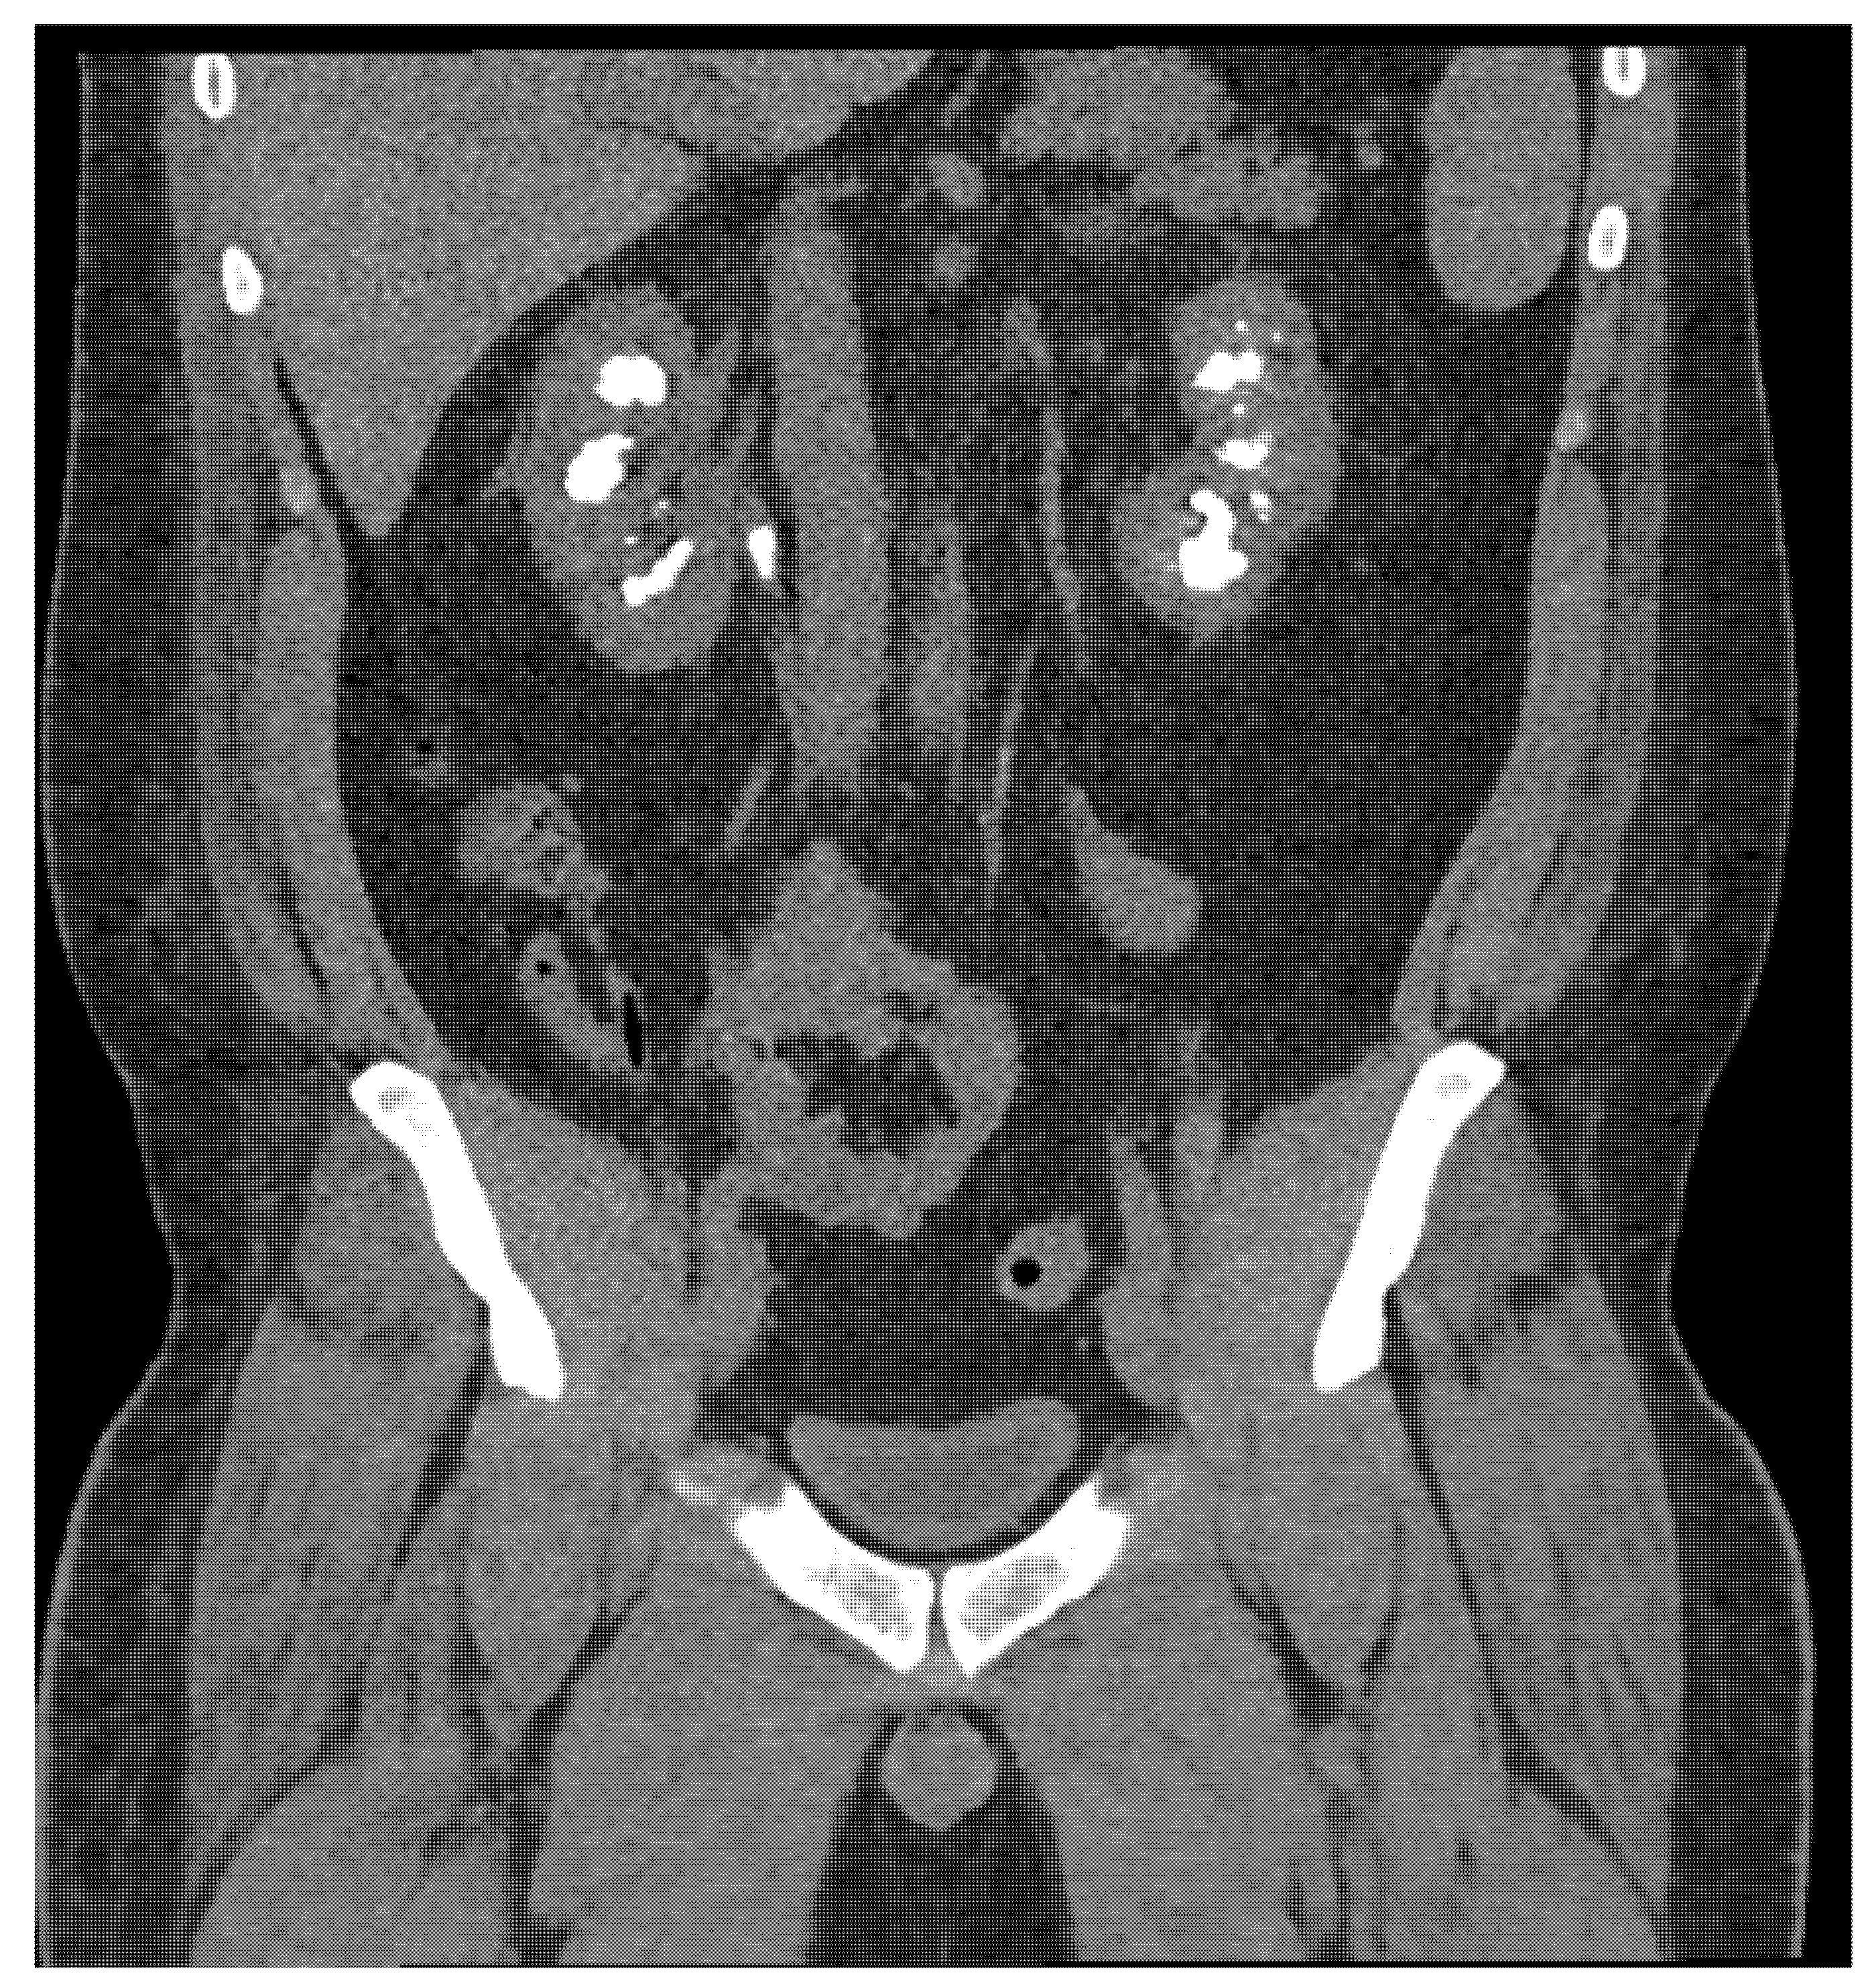

He was transferred to the Mayo Clinic due to severe electrolyte abnormalities in October 2017. His labs were notable for a Cr of 1.95 (eGFR 49 mL/min/1.73 m2), potassium of 2.6 mmol/L, bicarbonate 26.5 mmol/L, magnesium of 0.5 mg/dL, and calcium of 5.2 mg/dL. His parathyroid hormone (PTH) was 96.3 pg/mL, vitamin D 27 ng/mL, and 1,25-dihydroxy vitamin D 47 pg/mL. Of note, the patient had had a computational tomography of this neck in the past to evaluate his elevated PTH. This showed no parathyroid adenomas or masses. CT of the abdomen and pelvis during admission was notable for extensive calcifications of the medullary regions of both kidneys consistent with nephrocalcinosis and an obstructing 1 cm right renal pelvis stone (Figure 1). The patient had a ureteral stent placed for the obstructing stone and his electrolytes were normalized with supplementation. He was discharged on magnesium oxide 800 mg four times a day, calcium carbonate 1000 mg three times a day, amiloride 5 mg daily, colchicine 0.6 mg twice a day, and allopurinol 100 mg daily, and advised to continue HCTZ 12.5 mg daily and potassium chloride 15 mEq twice a day.

Figure 1.

CT scan on presentation demonstrating bilateral large volume stone burden and an obstructing 1 cm right ureteropelvic junction stone. Burden of stone disease consistent with nephrocalcinosis.